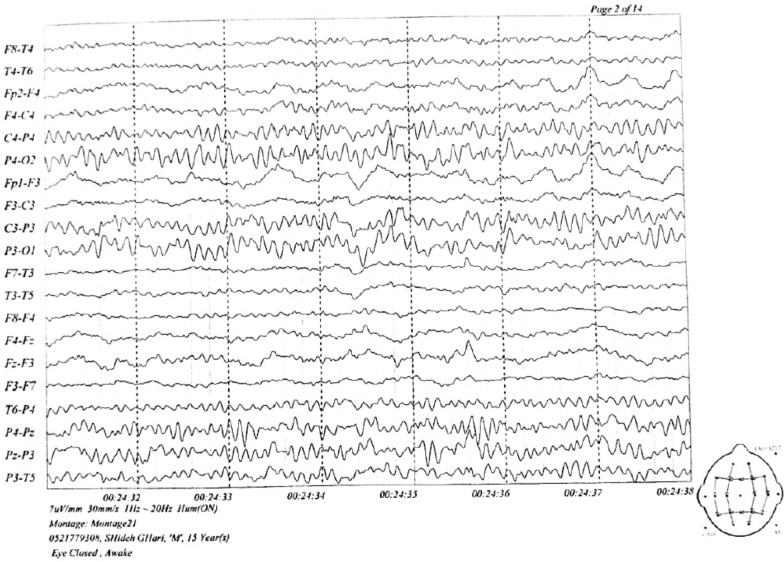

Diagnostic medical imaging

To examine the patient more closely, computed tomography (CT) scan and magnetic resonance imaging (MRI) of the brain; chest X-ray (CXR); ultrasound of the thyroid, abdomen, and pelvis; and electroencephalogram (EEG) tests were requested and performed.

The MRI findings were normal, but several diffuse cortical hyperintensities were observed, consistent with the patient’s history of anti-NMDAR encephalitis. This may indicate an inflammatory process related to a relapse. However, the overall normal findings and the absence of abnormalities in complementary imaging studies, including brain CT, chest X-ray, and ultrasounds, suggest no concurrent structural or systemic pathology. The EEG was also evaluated and found normal (Figs. 1, 2, 3).